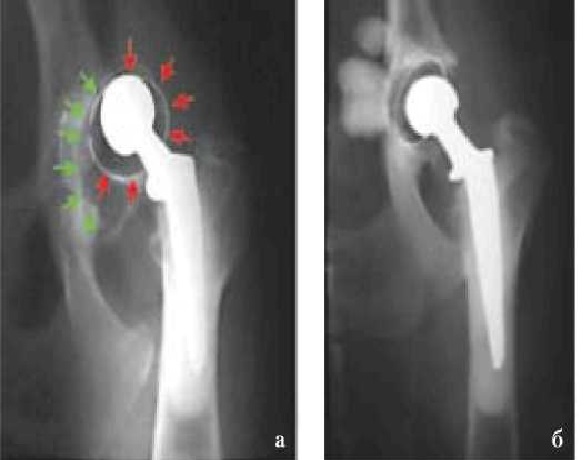

Смещение чашки эндопротеза (вертлужного компонента) без признаков АН было отмечено в 5 из 13 (38,5 %) случаев (рис. 1) в среднем через 75,5 (58. 104) сут после операции.

При данном осложнении прибегали к ревизионному эндопротезированию с дополнительной расточкой суставной впадины и последующей фиксацией чашки. В двух случаях выполнена костная пластика дорсального и краниолатерального края суставной впадины, а в одном эндопротез пришлось удалить. АН обоих компонентов эндопротеза наблюдали в 6 из 15 случаев (40 %) (рис. 2), причем у одного животного — двустороннюю в разные промежутки времени.

Рис. 1. Рентгенограмма. Вывих вертлужного компонента эндопротеза ( смещение чашки показано стрелками) без признаков асептической нестабильности (а). Ревизионное эндопротезирование с повторной фиксацией чашки эндопротеза (б)